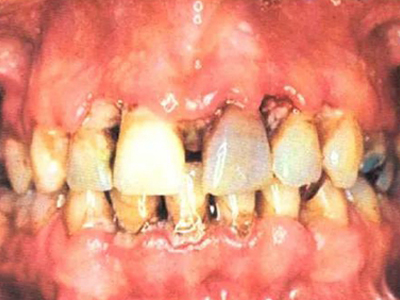

急性坏死性溃疡性龈炎起病急,病程短,常为数天至1-2周,以龈乳头和龈缘的坏死为其特征性损害,尤以下前牙多见,初起时龈乳头充血水肿,个别龈乳头顶端可发生坏死性溃疡,上覆有灰白色坏死物,中央凹下如火山口状。龈缘如虫蚀状,坏死区出现灰褐色假膜,擦去后可见出血创面。龈乳头被破坏后与龈缘成一直线,如刀切状。病损一般不波及附着龈,患处牙龈极易出血,疼痛明显并有腐败性口臭。

重症患者可有低热、疲乏等全身症状,并可伴有下颌下淋巴结肿大和压痛。有的患者可能进展为坏死性龈口炎、坏死性溃疡性牙周炎等疾病,从而导致牙周袋形成、牙槽骨吸收和牙齿松动。